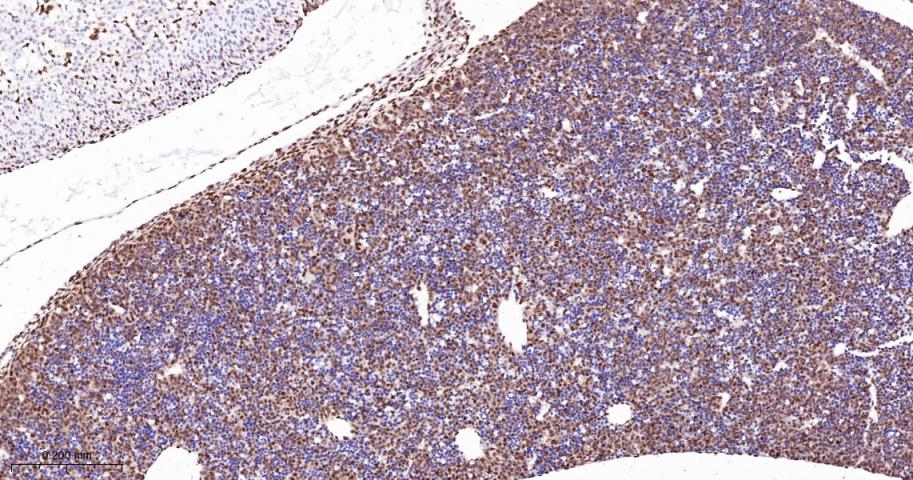

Paraformaldehyde-fixed, paraffin embedded Human Spleen; Antigen retrieval by boiling in sodium citrate buffer (pH6.0) for 15 min; The section was incubated with PTBP1 Monoclonal Antibody, Unconjugated (bsm-60550R) at 1:200 overnight at 4°C, followed by conjugation to the bs-0295G-HRP and DAB (C-0010) staining.

Paraformaldehyde-fixed, paraffin embedded Rat Spleen; Antigen retrieval by boiling in sodium citrate buffer (pH6.0) for 15 min; The section was incubated with PTBP1 Monoclonal Antibody, Unconjugated (bsm-60550R) at 1:200 overnight at 4°C, followed by conjugation to the bs-0295G-HRP and DAB (C-0010) staining.

Paraformaldehyde-fixed, paraffin embedded Mouse Spleen; Antigen retrieval by boiling in sodium citrate buffer (pH6.0) for 15 min; The section was incubated with PTBP1 Monoclonal Antibody, Unconjugated (bsm-60550R) at 1:200 overnight at 4°C, followed by conjugation to the bs-0295G-HRP and DAB (C-0010) staining.